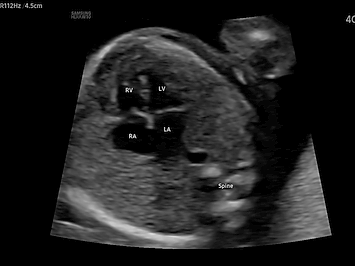

아이들 중에 절반 이상이 이 심장기형으로 사망하고 있다. 치명률이 높기 때문에 자세히 보아야 한다. 위험도는 신경관 결손보다 4배, 심각한 염색체 이상보다 6배나 더 높게 발생한다. 태어난 지 1년 이내에 높게 발생하는 선천적인 심장기형은 4가지나 있다. ventricular septal defect, coarctation of the aorta , transposition of the great arteries , tetralogy of fallot 심장초음파의 정확도가 높음에도 불구하고 임신 2 삼분기에 기형을 진단하는 경우는 매우 낮다. 보통 4 chamber view로 태아 심장으로 관할하고 있기 때문이다. 이 검사 view로 만으로는 위에 열거한 심장기형을 확실하게 찾아내기 어렵다. 그래서 targeting sono나 fetal echocardography를 할 수 있어야 한다.

20주~28주 가 가장 이상적이다. 그 이전의 시기는 태아의 구조물 크기가 작아 정확하게 눈으로 확인하기 어렵고, 이 시기가 지나면 태아의 늑골이 석회화가 증가하고 상대적으로 양수의 양이 감소하며 태반의 두께가 두꺼워지므로 초음파 빔이 통과하기 어려워 완벽한 검사를 기대하기 어렵다. 확인할 수 있는 가장 빠른 시기에 정확하게 진단을 내리고 그 뒤에 확인하기 어려웠던 부분들은 계속해서 주기적으로 관찰을 요한다. 소아나 성인과는 달리 태아는 계속 태동을 하며 위치를 바꾸기 때문에 항상 일정한 단면을 얻을 수 없으므로 반드시 태아의 위치를 확인하고 위치에 따른 심장의 내부구조를 입처적으로 형상화해야 원한느 단면을 얻을 수 있으므로 해부학적 구조의 상관관계를 알고 순차적인 분석을 시행하여야 한다. 태아의 심장 구조가 생기는 시기 배아에서 심장의 생성은 수정되고 2~7.5주 사이에 완성된다. embyogenesis동안 primitive cardiac tube 가 형성되고 primitive chamber로 진행되고 그 자체가 loop를 만들고 아주 복잡한 형샹으로 된 2개의 면으로 구분 지어진다. LMP10주 때부터는 심장 구조가 지속적으로 성장하고 성숙하게 되면 모든 구획이 끝난다. 따라서 다름 문제들은 10주 이상에서는 생성되지 않는다. transposition of the great arteriosus, artrioventrisular canal defect, tetralogy of fallot , ebstain's anomaly